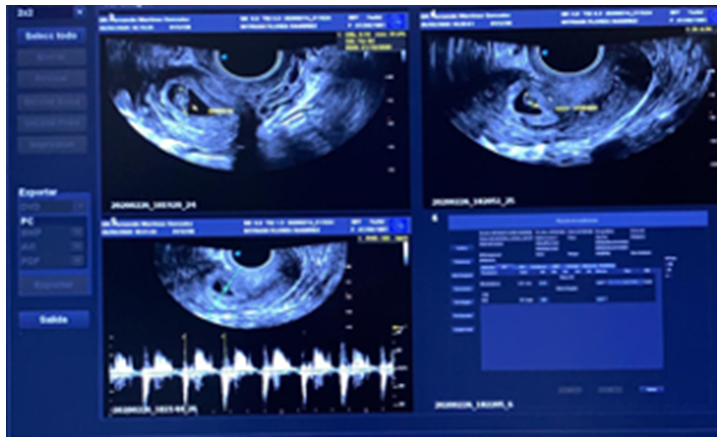

The endovaginal ultrasound reported a uterine cavity with a 14mm endometrial mid echo, bilaminar and homogeneous. Cervix with ovoid image of echogenic guresus wall, anechoic interior, gestational sac with image inside with a 4mm embryo, in relation to 6sdg pregnancy (Figure 1) (Figure 2). With beta fraction of 9145mUI/mL. Ectopic pregnancy is diagnosed.

Figure 2 Cervix doppler application gestational sac.

Endovaginal ultrasound reported a uterine cavity with a 10-mm endometrial, bilaminar and homogeneous echo. Cervix with ovoid image, anechoic interior, gestational sac with image inside with 9.7mm embryo, in relation to 8sdg pregnancy, with fetal heart rate (Figure 3).

Figure 3 Cervix with ovoid image, anechoic interior, gestational sac with image inside with 9.7mm embryo.